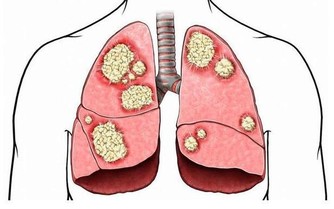

得了食管癌與賁門癌以後怎麼辦?這是個非常現實的問題。

當他自己在生活中體驗到進食發噎、並逐漸加重時,

他會很自然地意識到他得了食管癌或賁門癌。

他們患病後,即使在去醫院進行檢查之前,往往會自己做出—個幾乎很正確的診斷。當然也有—部分病人出現吞嚥困難症狀之後一直弄不清自己得了什麼病。